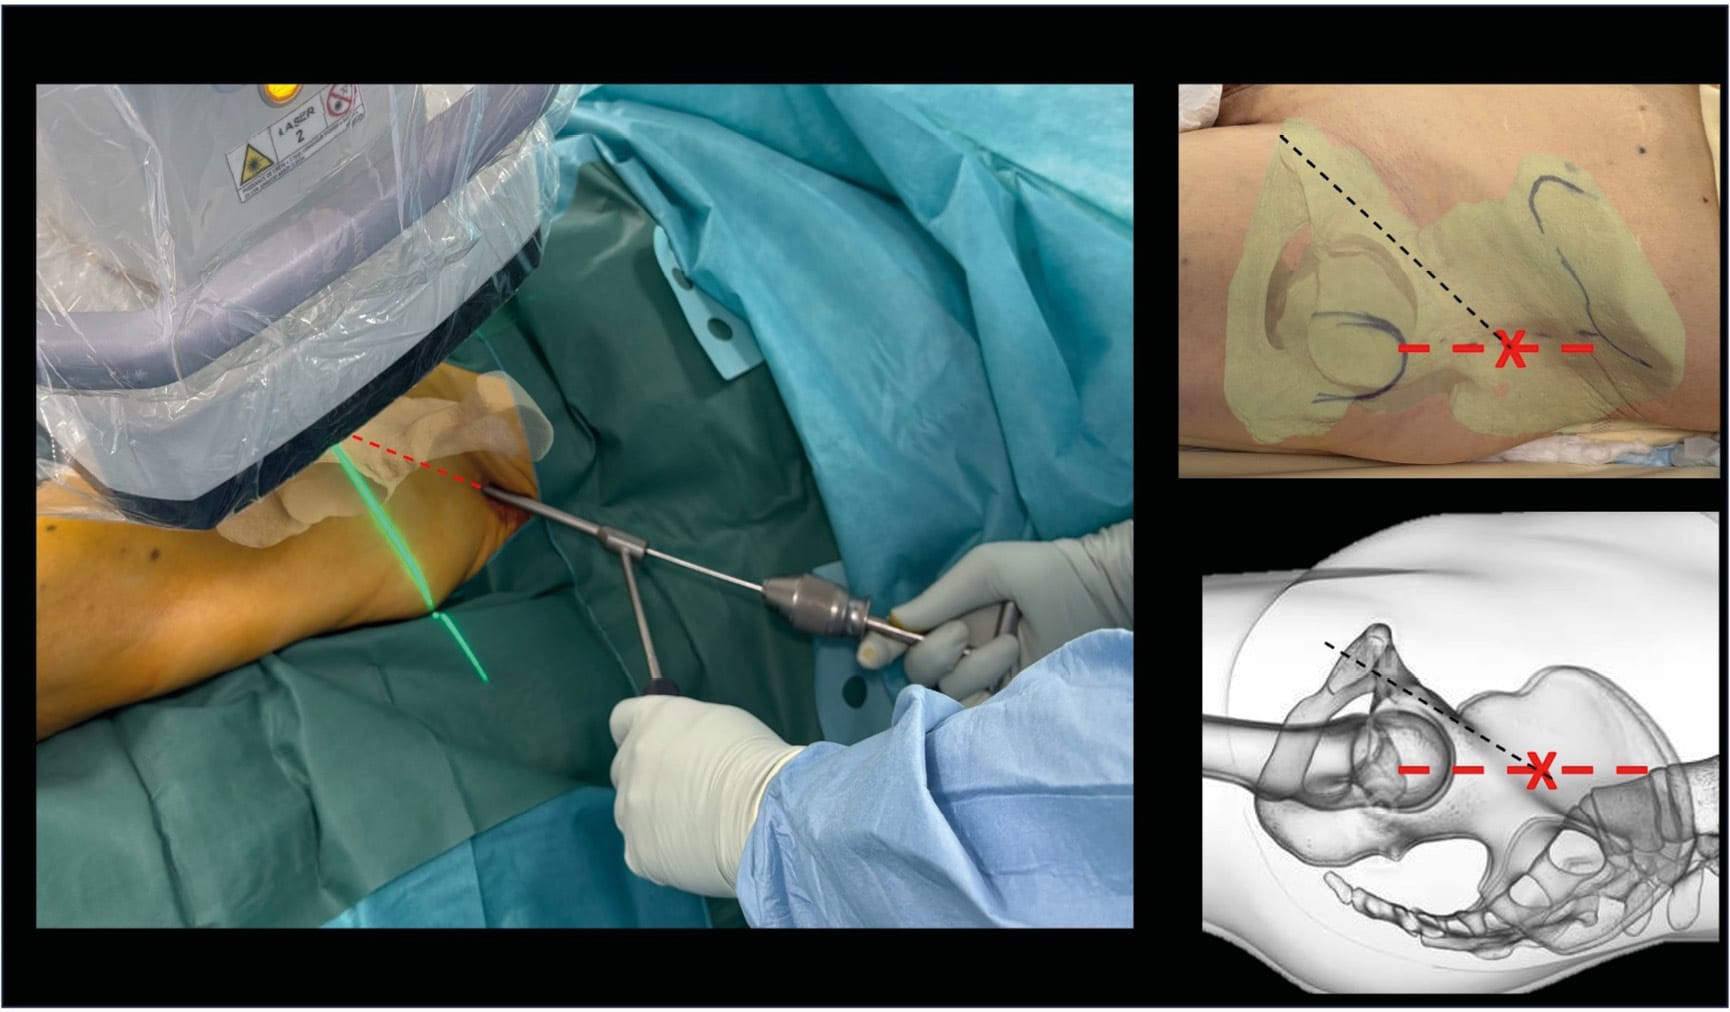

We prefer the use of guide wires with a "drill" tip rather than a "threaded" tip. Indeed, the "drill" wire offers the advantage of being fully dependent on the surgeon's hand (it does not progress with rotation), thus allowing a better feel of the bone densities while allowing a change of trajectory even during progression (Figure 5).

Its less aggressive tip (compared to the threaded wire) reduces the risk of false passage. Thus, a corridor can be found by using an American handle and making oscillating movements, allowing the wire to deform slightly (buckling) to follow a passage that is sometimes difficult to identify. This approach offers optimal tactile feedback, a technique that we employ very regularly (Figure 5).

Tips / Tricks: To incise at the optimal trajectory, we recommend, when beginning to gain experience, using a standard 2.0mm Kirschner wire through the skin to evaluate, under fluoroscopy, the ideal entry point and appropriate trajectory before making the scalpel incision. This approach helps avoid having to force through soft tissues in case of inadequate skin incision, which could complicate screw placement. In case of conflict with the contralateral thigh (extreme morphologies), one technique involves exploiting the creep (bending) of the guide wire. The radius of curvature thus generated allows for a trajectory that would be physically impossible to achieve with a straight wire (Figure 13). Using a curved wire or Metaizeau nail is an effective technique for finding the corridor when it is difficult or narrow (for example, to place the screw as far from the joint as possible), while limiting the risk of false passages [18] David G, Rony L, Moullac D, Letissier H, Di Francia R. The “Metaizeau trick” to facilitate medullary pubic ramus screw insertion: A technical note. Orthop Traumatol Surg Res OTSR 2024;110:103879. https://doi.org/10.1016/j.otsr.2024.103879.. Another technique involves using a cannulated drill bit at the entry point, then inserting a pre-curved Kirschner wire. The progression of the wire, followed by the drill bit, is performed repeatedly inside the corridor (Figure 14).